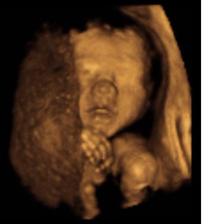

Mimísek :o)

ahojky již 5 měsíců jsme se s příítelem snažili o miminko ale stále nepřicházelo.jelikož často trpím na zánět močáku stále víc jsem se bála že to krásné miminko mít nikdy nebudu.kolem mě všechny mé kamarádky jsou bud těhotné nebo již už miminka mají a já čím dál víc moc a moc trpěla.12.11 jsem byla na preventivní gynekologické prohlídce kde jsem dopadlo moc dobře a dokonce mi pan doktor sdělil že mě může brzo očekávat s poz.testem.to mi malinko zvedlo naději že bych mohla být konečně tou maminkou.jelikož je moje sestra ve 4 měs.tak mi to moc přála a těší se na společ.mateřskou dovolenou.takže z této informace d doktora byla nadšená a věřila že tam mimísek už je.druhý den jsme šly společně na obídek ještě s kamarádkou Renatkou která má už taky dětičky.no a zakoupily mi test.bála jsem se ho udělat ale nakonec mě přesvědčily.bohužel byl negativní a moje naděje se opět rozplynula...:o(( poslední menses jsem měla 25.10 dne 20.11 jsem to měla dostat a strašně m bolelo břichu už 2dny před takže jsem nedoufala.renatka mi hned ráno psala že mi zbývá ještě jeden test tak at to testnu.ale já se bála a zárověn mě přeci bolelo břicho tak proč??nakonec mi to nedalo a test si udělala a najednou tam byla slábá ale přeci // nemohla jsem tomu uvěřit. Dne 21.11 jsem si uděla 2 test a opět // opět slabší.takže 3 pokus 22.11 a tam opět // už silnější.takže děsná radost.mám hlad jak vlk v noci nemohu spát ale je to nádherný pocit.zítra se objednám k doktorovi.všem kteří mají stejný pocit jako jáže to 5 měs.nejde určitě to nezahazujte ono si vás to miminko najde.velký díky patří mojí sestřičce která mě moc podporovala a nevzdávala moji naději a samozřejmě Renatce.holky bez vás bych to nezvládla mám vás ráda...